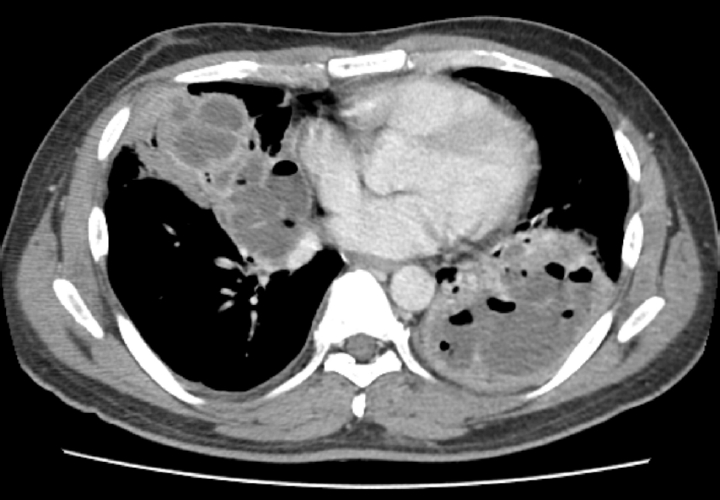

Empirical intravenous antibiotic therapy with piperacillin/tazobactam and levofloxacin was administered. On the second day of admission, the patient developed hemoptysis for which intravenous tranexamic acid was administered for 5 days, followed by oral maintenance. Clinical improvement was not achieved following a 7-day course of intravenous antibiotics, with the clinical course marked by unresolved febrile episodes and persistent leukocytosis. Furthermore, a follow-up chest CT on hospital day 7 revealed aggravation of the internal cavitations and abscess formation within the consolidative lesions of the right middle lobe and both lower lobes (Fig. 2). The failure of conservative management to arrest the necrotizing process, combined with the high risk of secondary sepsis from the poorly drained, inspissated purulent material, prompted the decision to escalate to video-assisted thoracoscopic surgery (VATS) for definitive source control and debridement. Intraoperative examination revealed dense pleural adhesions and extensive necrosis of the lung parenchyma. Thick, yellowish, and inspissated purulent material was drained from the abscess cavities located in the right middle and left lower lobes (Fig. 3). Given the deep and multiloculated nature of the abscesses, wide unroofing was performed via wedge resection using an endoscopic stapler and ultrasonic shear to ensure adequate drainage. Subsequently, thorough decortication and irrigation of the thoracic cavity were performed. A closed thoracostomy was performed with chest tube and Hemovac placement. Histopathological examination of the lung tissue revealed acute fibrinous and organizing pneumonia, consistent with chemical exposure.

Fig. 2.

Chest computed tomography on day 7 revealing multiloculated abscesses involving right middle and left lower lobes.

Fig. 2. Chest computed tomography on day 7 revealing multiloculated abscesses involving right middle and left lower lobes.